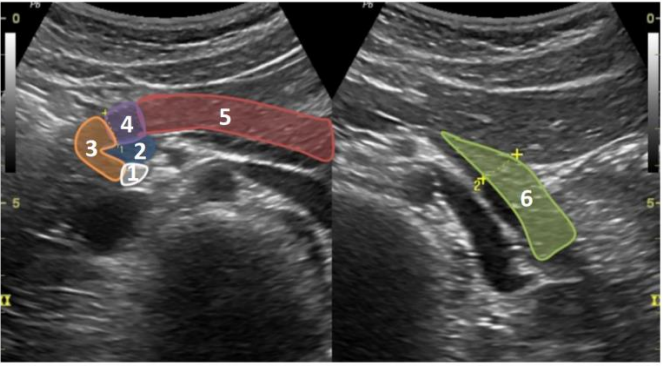

COM BASE NA IMAGEM A SEGUIR, RESPONDA AS QUESTÕES 28 E 29.

Fonte: MANUAL BASICO DE UTRASSONOGRAFIA – ESCOLA PAULISTA DE MEDICINA/2013

Quais órgão (s) está (ão) em evidencia na imagem?